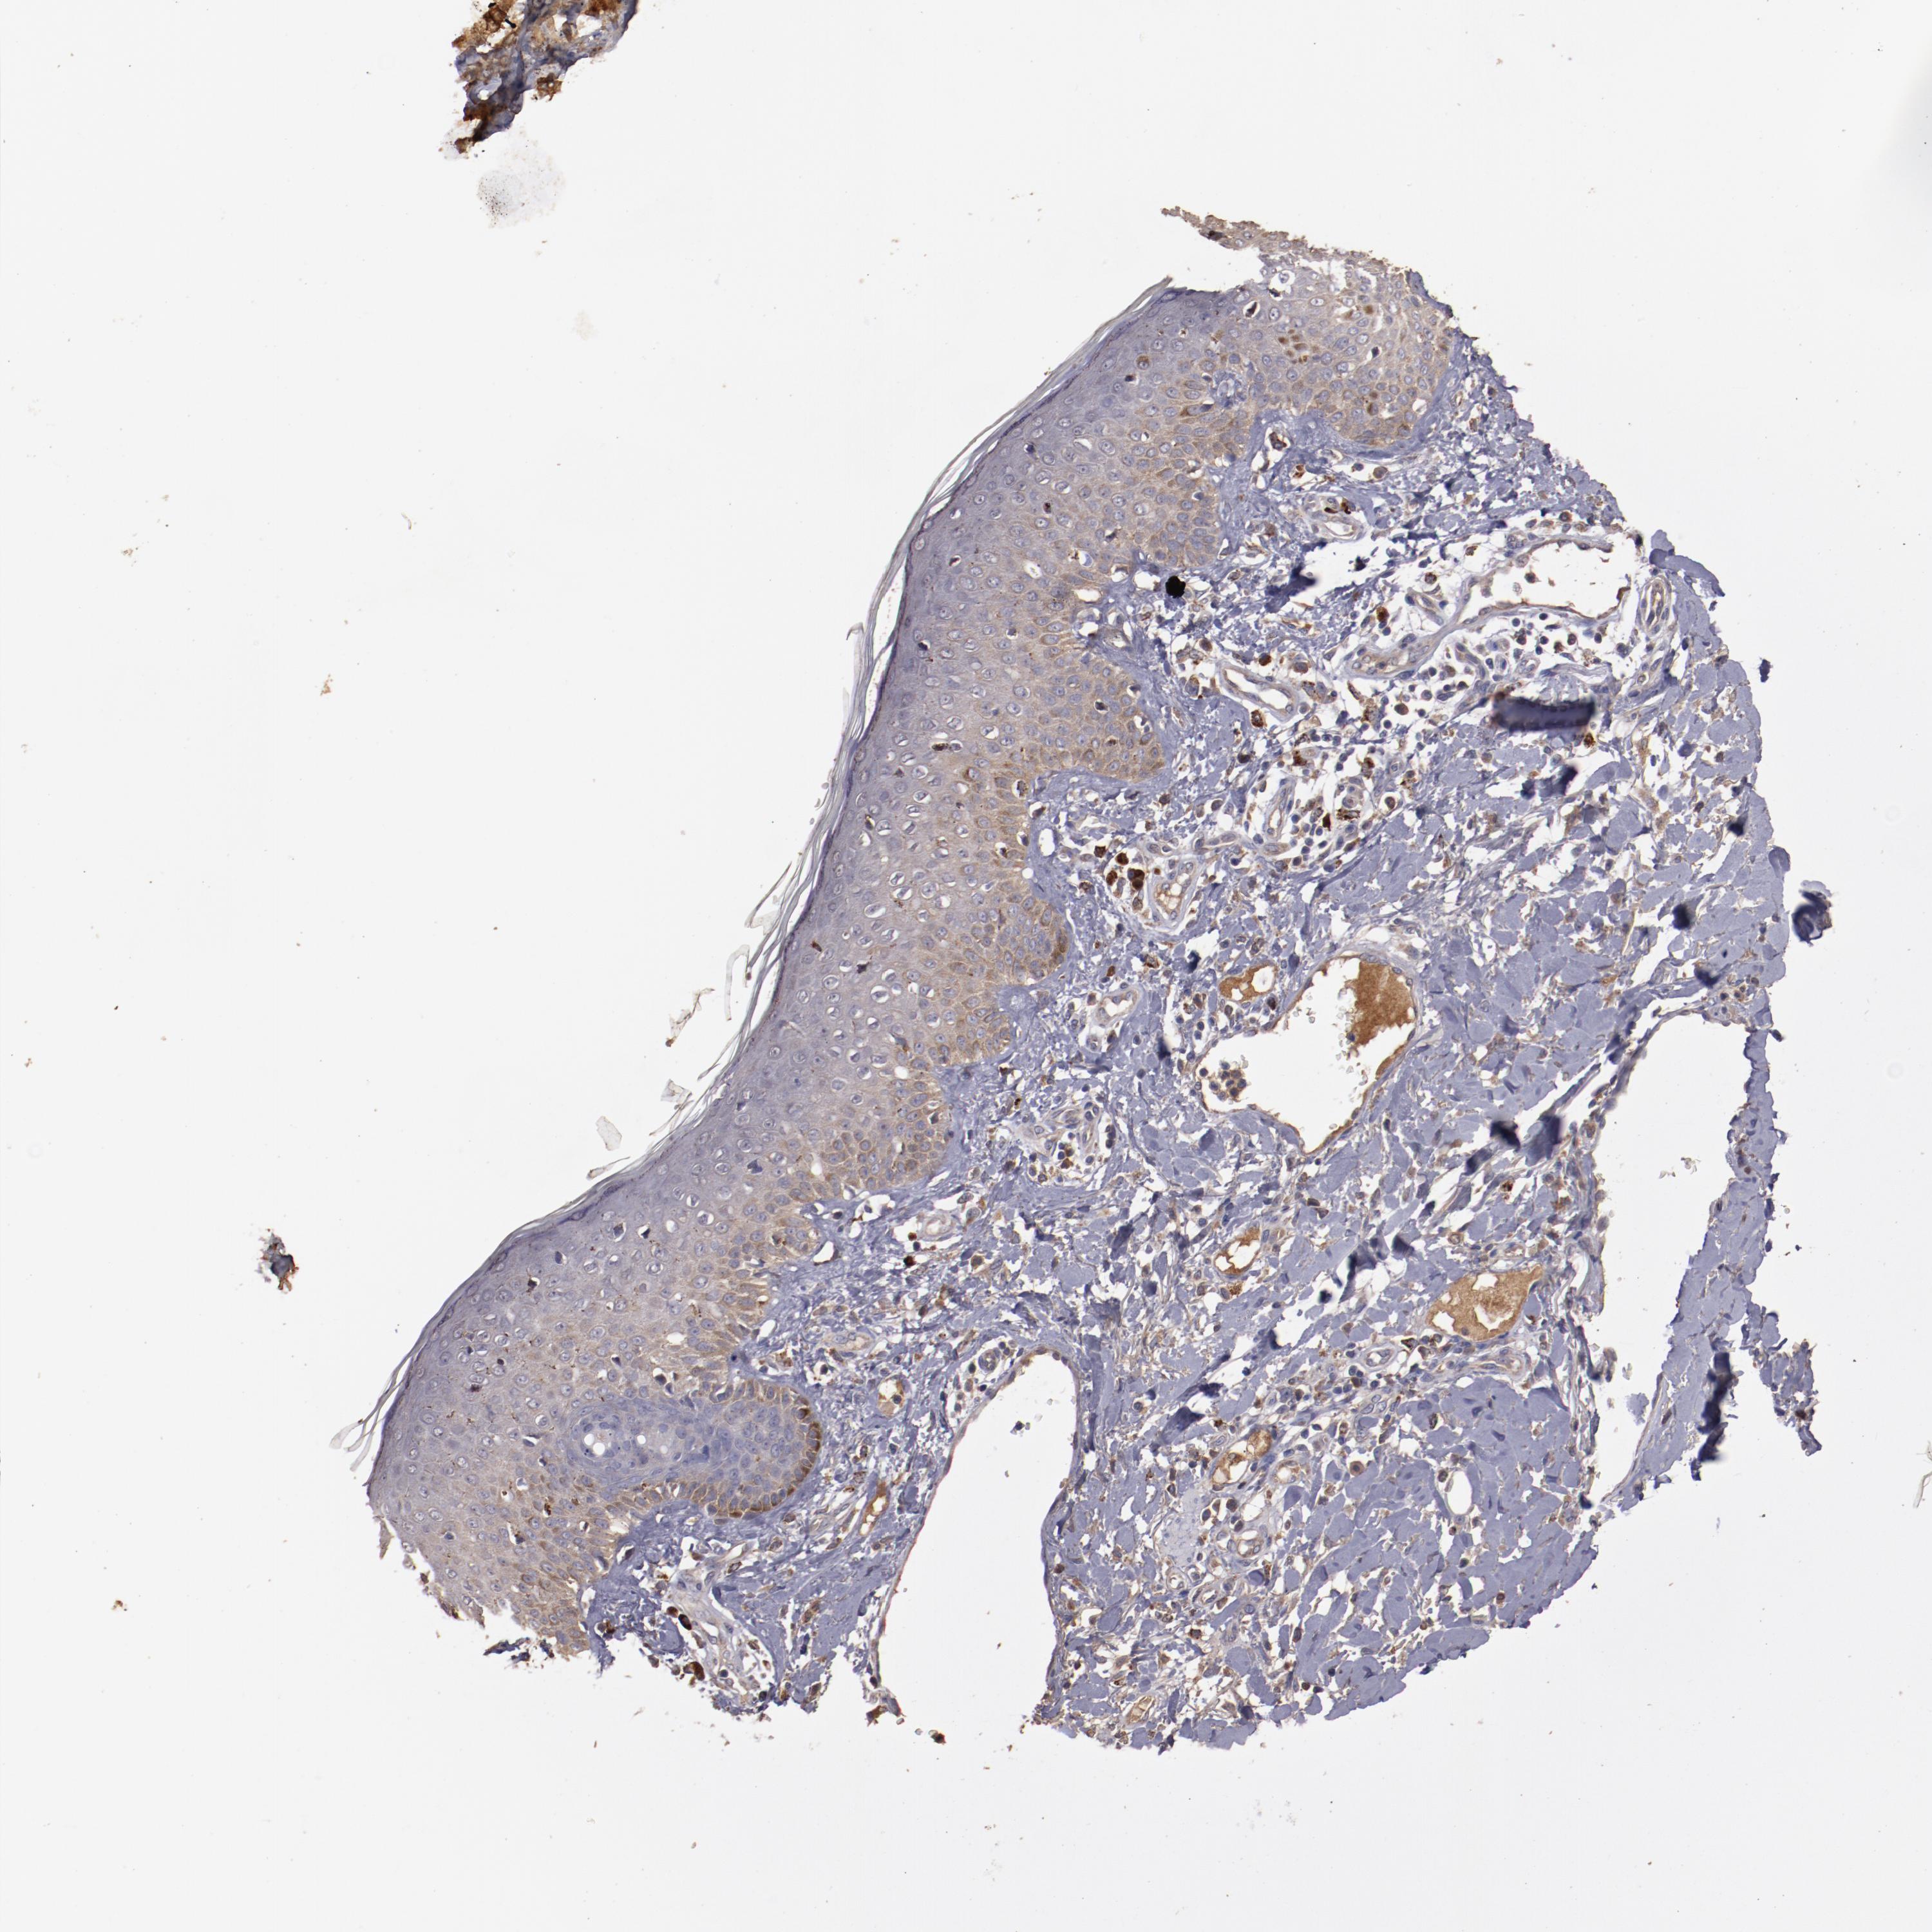

SKIN CANCER - Protein expressioni

A mouse-over function shows sample information and annotation data. Click on an image to view it in a full screen mode. Samples can be filtered based on level of antibody staining by selecting one or several of the following categories: high, medium, low and not detected. The assay and annotation is described here.

Antibody staining in the annotated cell types in the current human tissue is reported as not detected, low, medium, or high, based on conventional immunohistochemistry profiling in selected tissues. This score is based on the combination of the staining intensity and fraction of stained cells.

Each image is clickable and will lead to virtual microscopy that enables deeper exploration of all samples and also displays staining intensity scores, fraction scores and subcellular localization as well as patient and tissue information for each sample.

Antibody HPA002945

Staining

High

Medium

Low

Not detected

Intensity

Strong

Moderate

Weak

Negative

Quantity

>75%

75%-25%

<25%

None

Location

Nuclear

Cytoplasmic/membranous

Cytoplasmic/membranous,nuclear

Squamous cell carcinoma, NOS

Basal cell carcinoma